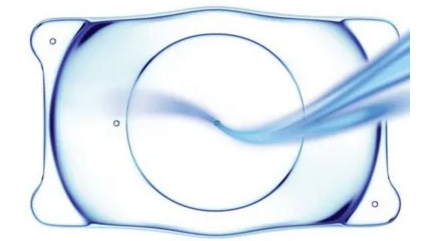

ICL晶体植入术

ICL晶体植入术就是在角膜边缘微创一个小口,把适合患者度数的ICL晶体植入眼内,具体位置是在眼睛的虹膜后,晶状体前。进入眼睛后,晶体会缓慢地展开,相当于给眼睛里面戴了个隐形眼镜。ICL晶体材料的生物相容性非常好,无需去切削角膜组织,晶体相对 ,即植入的晶体将来可以取出,同时具有视觉质量高,医治范围广等优点。手术切口小,可自行闭合,没有疼痛感。

ICL晶体植入虽然是高度近视患者的主流手术方式,但越来越多的患者包括角膜条件不适合激光手术的近视患者,选择ICL晶体植入手术,并成功摘掉了眼镜。